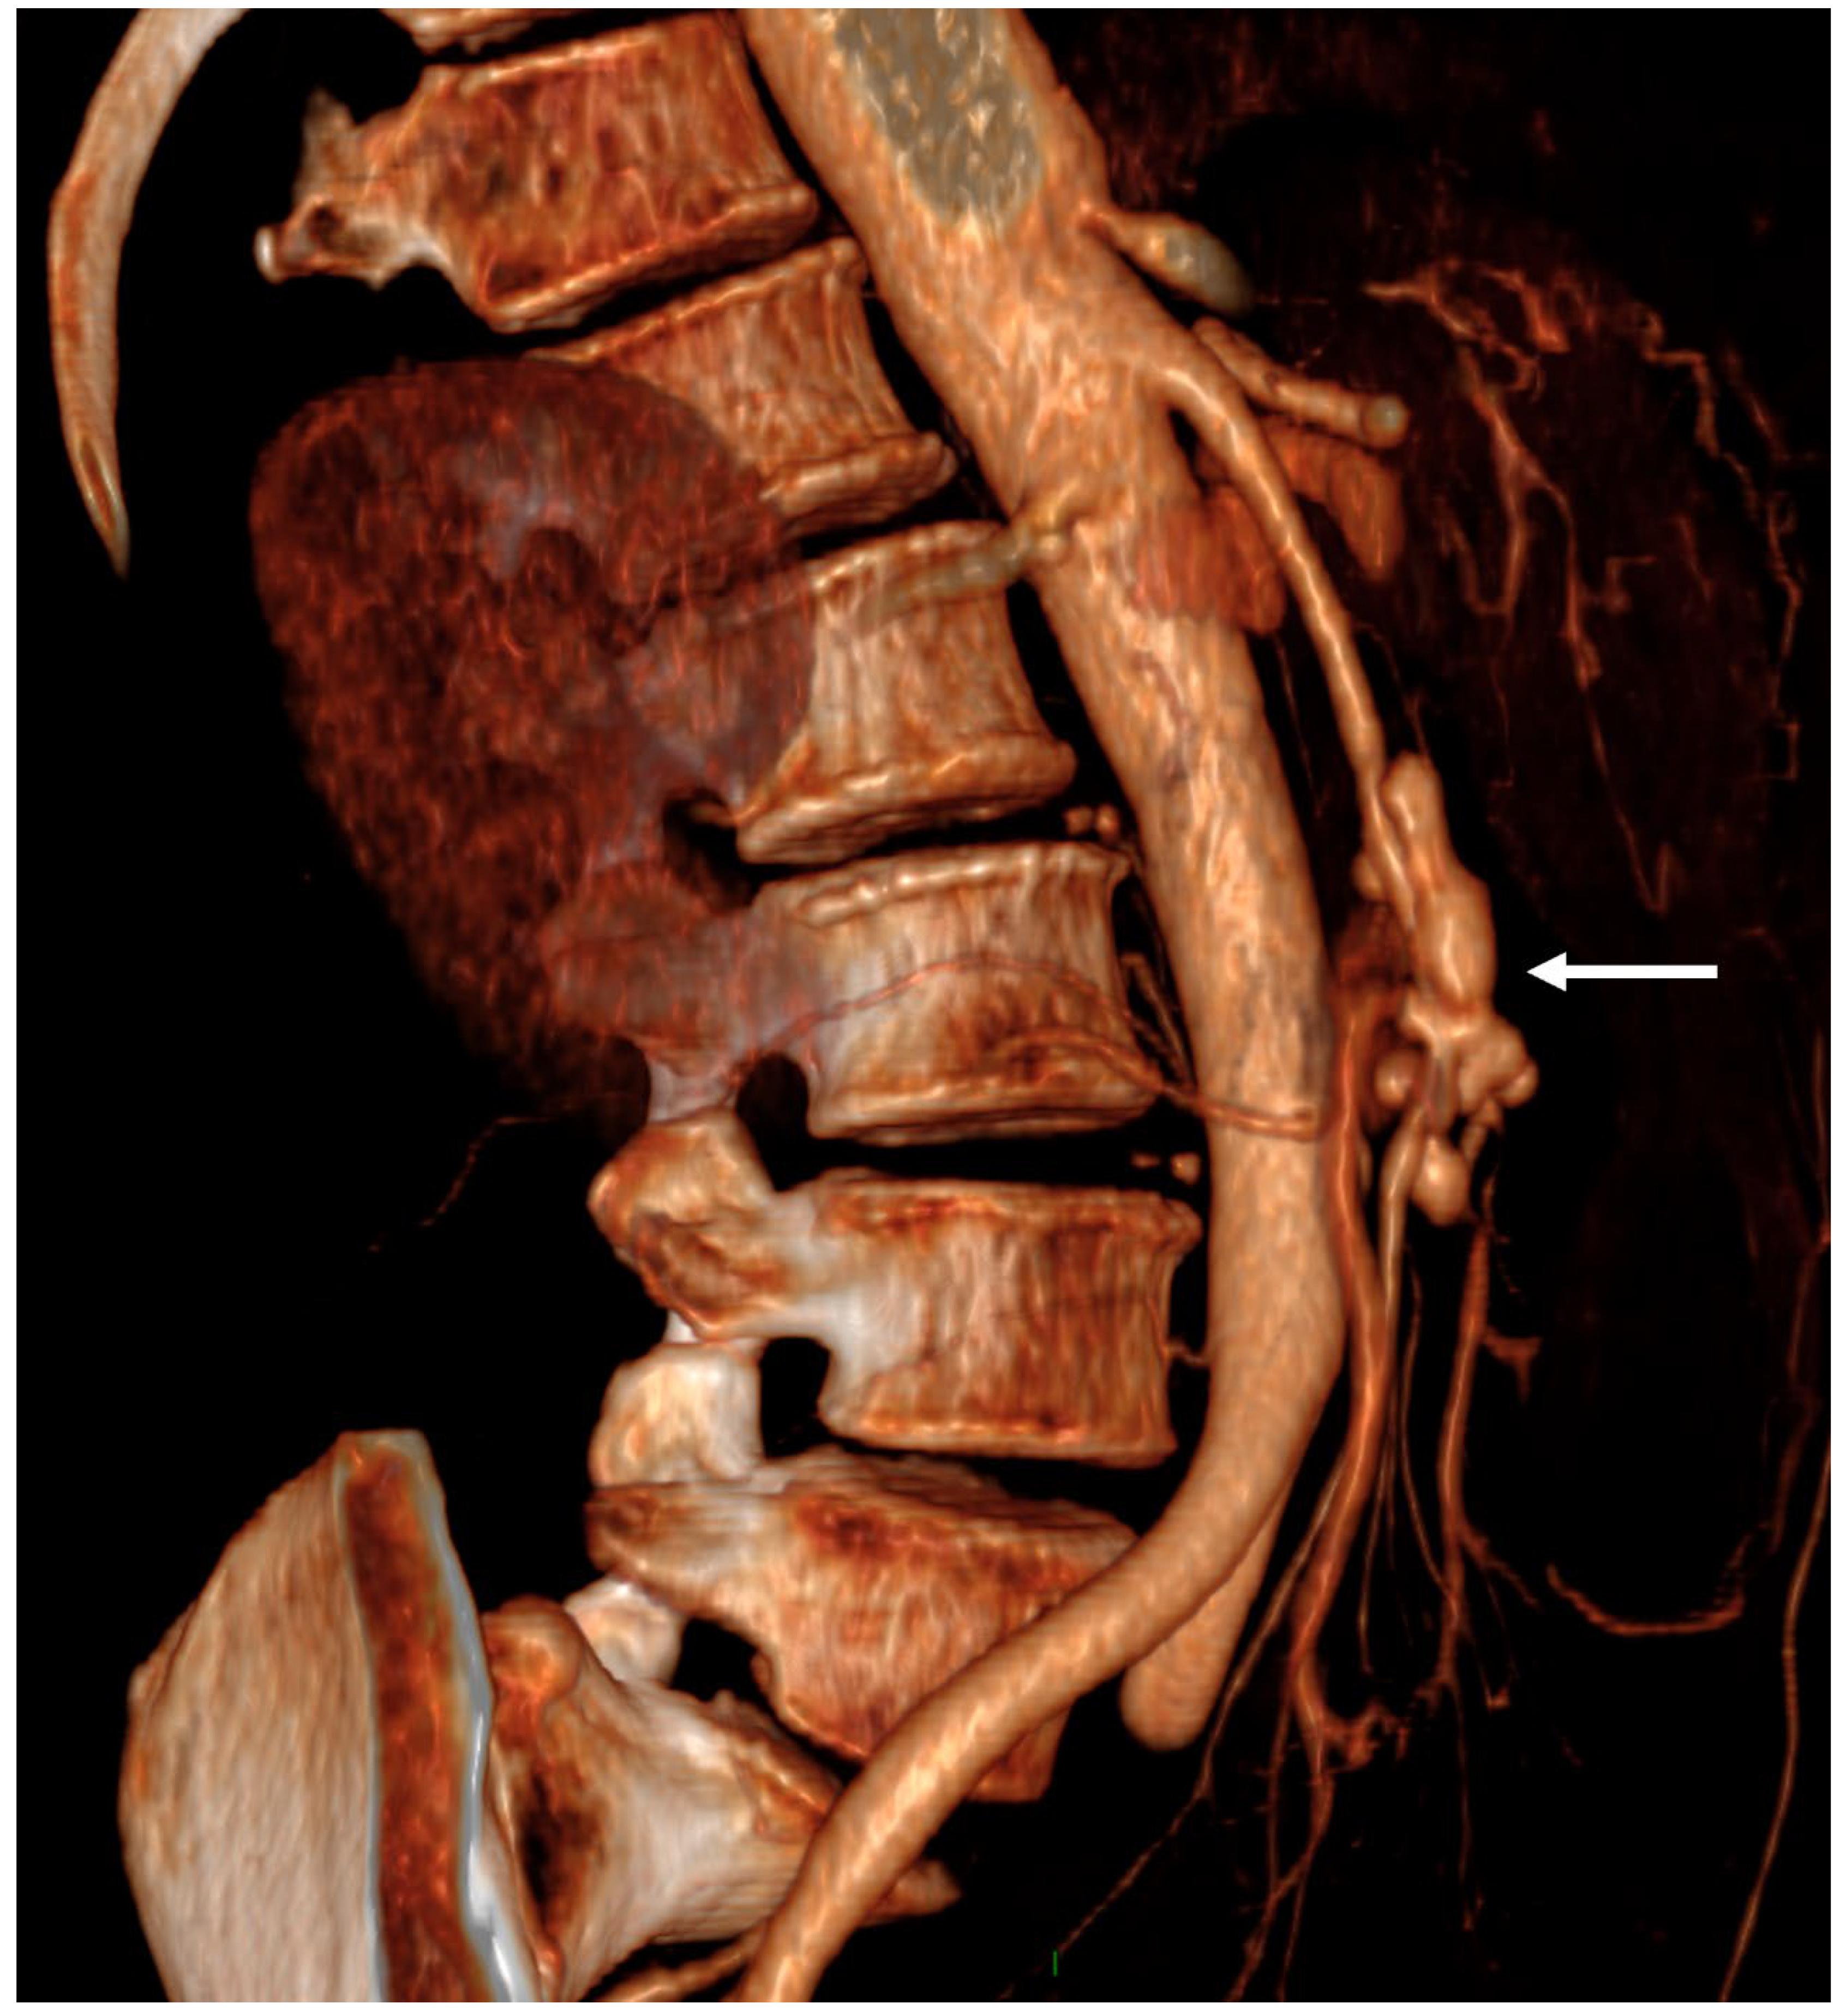

- Boukobza, M.; Raffoul, R.; Rebibo, L.; Khalil, A.; Laissy, J.P. Splenic Artery Infectious Aneurysms in Infective Endocarditis—An Observational Study and Comprehensive Literature Review. Ann. Vasc. Surg. 2024, 99, 389–399. [Google Scholar] [CrossRef]